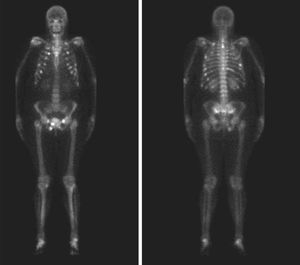

CaseA 53 year woman, without notable history, came to the emergency room presenting mechanical, intense pelvic pain and inability to stand or walk. Urgent laboratory analysis highlighted an alkaline phosphatase value of 398U/l (30–120), the rest of the blood count and biochemistry values were normal. AN AP radiograph of the pelvis showed osteopenia with no other findings. The patient was admitted and a second set of laboratory tests requested: phosphate 1.2mg/dl (2.5–4.5), alkaline phosphatase 395U/l (30–120), 1.25 vitamin D3 32.7ng/ml (30–40), phosphaturia, 1436.00mg/24h (400–1300). Other values were normal. An isotope bone scan was requested (Fig. 1), as were a pelvic CT (Fig. 2) and a pelvic MRI. A subsequent physical examination demonstrated that the patient had hard, painless, 2cm×2cm erythematous and bullous lesions on the sole of her left foot. Suspecting a phosphaturic tumor an octreotide scintigraphy was requested and found normal. We requested an MRI of the foot (Fig. 3) and removed the lesion. The pathologic diagnosis was: mixed connective tissue variant mesenchymal tumor. After removal of the tumor, the patient returned to normal blood and urine phosphate values and no new fractures occur.